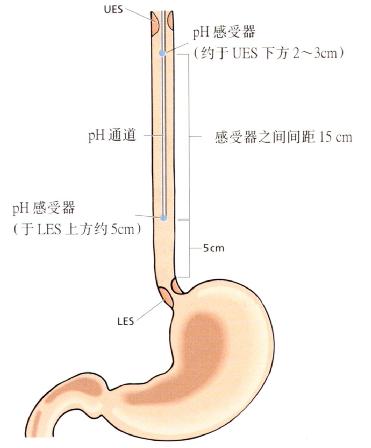

为检测可能引起喉炎和/或肺部疾病的近端食管反流,应行双通道24小时pH监测。其中一个pH监测。其中一个pH感受器应置于LES上方5cm,另一感受器置于食管近端(UES下方2-3cm)(见8.2)。

图3.20检测高位反流,pH感受器置于食管内的位置。

双通道24小时pH监测(图3.20):

运用双通道的电极可检测近端酸反流,其中一个pH感受器置于LES上方5cm,另一感受器置于近端食管(UES下方2-3cm)(见8.2)。